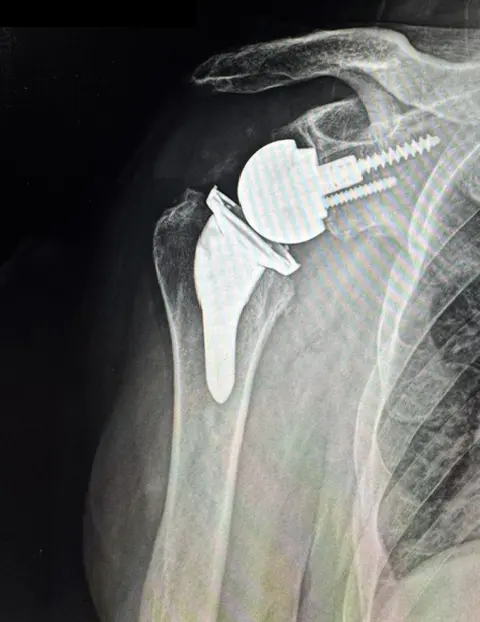

Reverse Shoulder Replacement

Dr. Vizzi proudly provides InSet® shoulder replacement